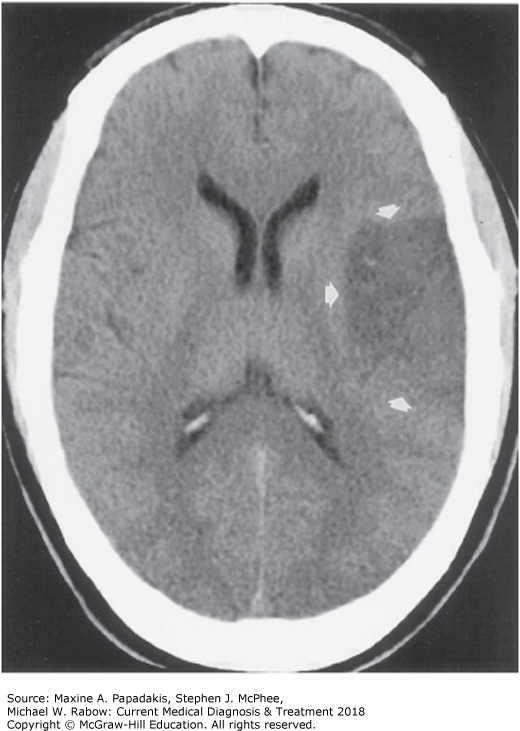

Acute left MCA infarct on MRI of a 65-year-old hypertensive man. The MRI demonstrates increased signal intensity (arrows). Abnormalities in MRI occur before those seen on CT during ischemic strokes.